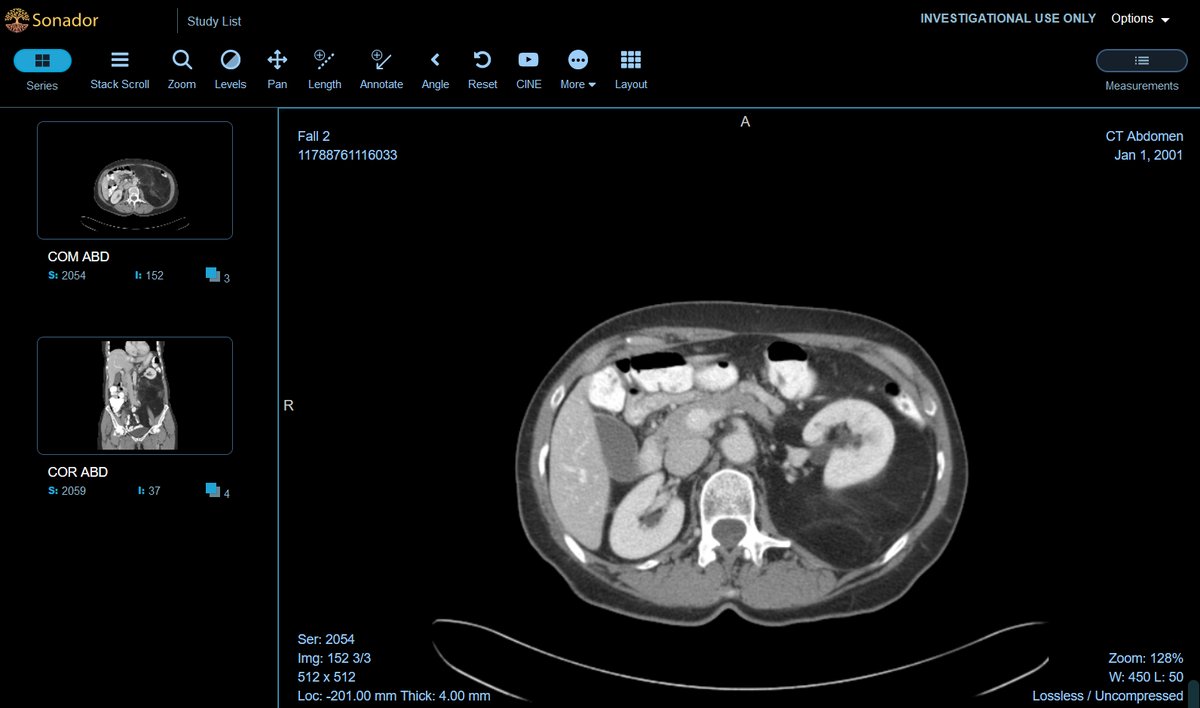

This article provides a high-level overview of DICOM, its components and terminology, and how the tools within the Sonador platform can be used to work with two and three-dimensional DICOM data for building healthcare software applications.

Because this article focuses on the Sonador platform (a cloud-native set of programs used to build medical imaging applications), DICOM concepts will be illustrated using Orthanc; the Open Health Imaging Foundation (OHIF) Viewer; and related tools such as MONAI, SonadorAI, and Sonador3D.

As DICOM is file-based, the metadata for these relationships are defined within individual DICOM file "instances." Higher level resources such as collections of images (called series), studies, and patients are modeled from the metadata of instances. The figure at right shows how Orthanc interprets the DICOM resource model:

- An individual DICOM file represents an instance and is comprised of headers and pixel data

- Each series contains a set of instances

- Each study contains a set of series

- Each patient has a study and may have a set of studies

For software developers working with imaging resources, the DICOM series is one of the most common resources used for visualization or machine learning use-cases. It (usually) represents an imaging scan/acquisition and a cohesive piece of data. For 2D scans (such as a chest x-ray) there will be a single image; while for 3D scans (such as MRI or CT), there will be a stack of images that can be constructed into a volume.